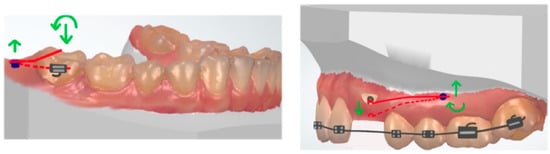

7. Space Closure

10. Molar Uprighting